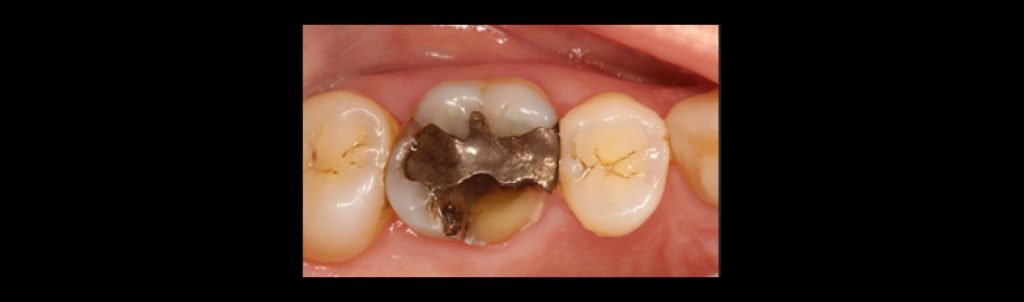

Fracture line cracks penetrate dentin. They may appear as stained lines with no enamel separation or as true splits in enamel. Symptoms may include biting pressure, release pain, and cold sensitivity. Fracture lines in posterior teeth that cross marginal ridges are more concerning than those that remain within the confines of the occlusal surface.

Fracture lines are commonly observed in teeth with extensive restorations, resulting from the weakening of the natural tooth structure. Severity and prognosis cannot be fully determined until pulp testing and definitive excavation are performed.